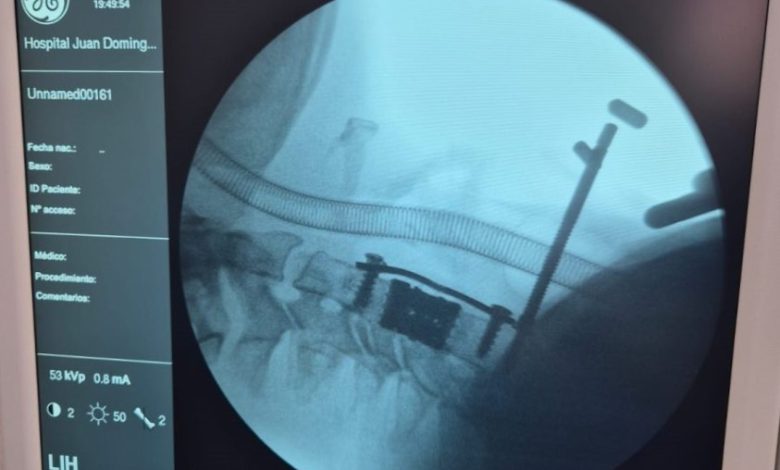

Por primera vez en la historia del hospital, un equipo multidisciplinario del Policlínico Regional “Juan Domingo Perón” de Villa Mercedes realizó una cirugía de corpectomía cervical, un procedimiento de alta complejidad que marca un antes y un después en la neurocirugía del sistema público de salud provincial.

La operación consistió en extraer el cuerpo vertebral afectado por una lesión medular severa y reemplazarlo por una prótesis especialmente diseñada, provista por el Ministerio de Salud a través de las empresas Zion–Corpomedica.

La corpectomía cervical es una técnica quirúrgica que requiere precisión milimétrica y equipamiento de última generación. A través de una vía anterior en el cuello, se extrae uno o más cuerpos vertebrales y se reconstruye la estructura ósea mediante injerto o prótesis, liberando la presión sobre la médula espinal.